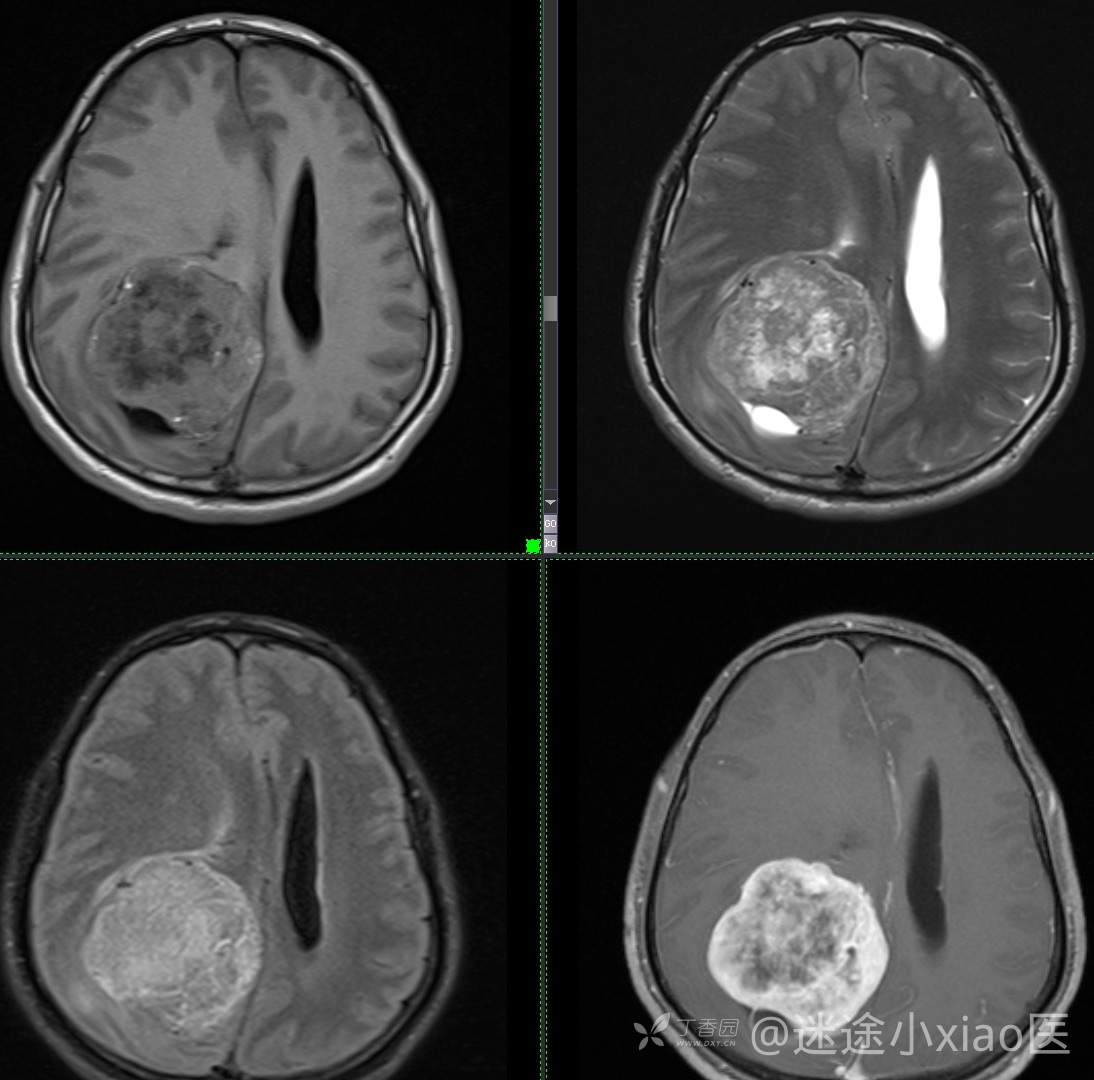

病例头颈组14:中年男性,显著强化病灶,如何考虑(结果公布)

如此典型病例,平扫即可诊断(结果公布)

患者年龄:43

患者性别:男

简要病史:头痛3月余,查体无殊